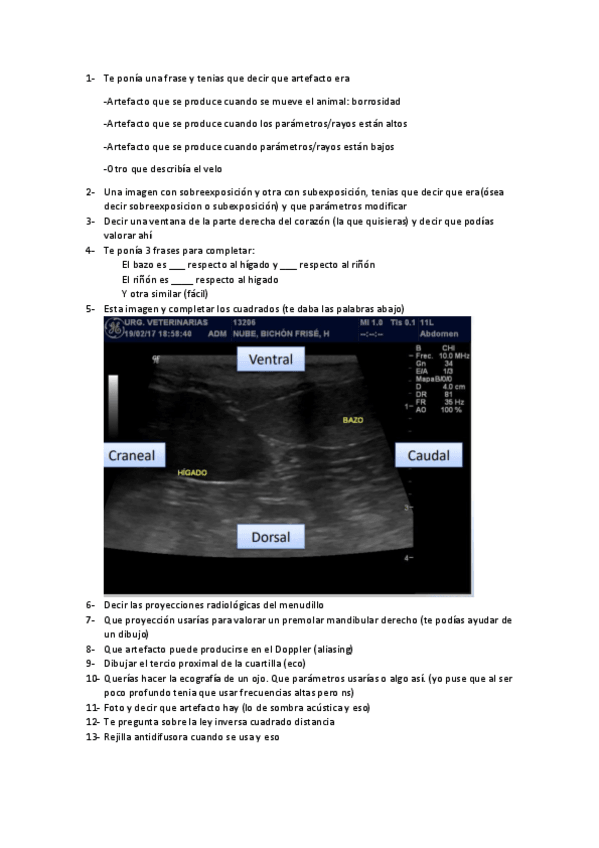

ANATOMIA-RADIOLOGICA-DE-LA-CABEZA-DEL-PERRO-Y-GATO.pdf